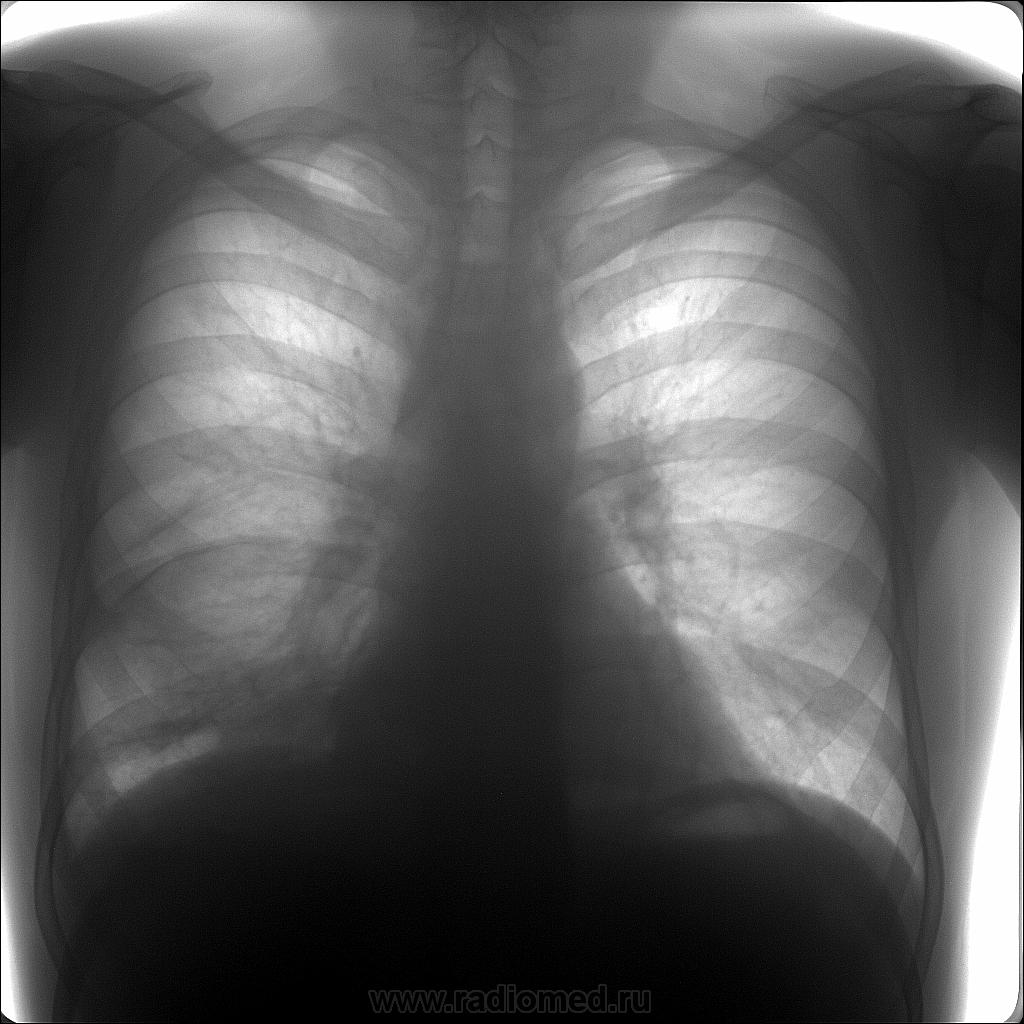

Надеюсь, что плеврит.Если нет, то я не знаю.По-моему, картина типичная.Пункцию делали?

Плеврит - то плеврит... Насчет пункции не знаю, в выписке упоминаний о ней нет. Вероятно, не делали. Думаю, плеврит был ТБС этиологии.

Вы думаете дебютировал Его Величество с плеврита, а спустя год выдал очаги?

Именно так и думаю. Показал свое "мурло".

И к тому-же осумкованный. Передний и задний

Осумкование уже должно было навести на мысль о ТБС.

1. У Вас, в процессе лечения динамика налицо, ну, осталось, по всей видимости, некоторое количество "осумкованного" сзади паракостально, возможно, возможно, и нет, может плевра утолщена, да кое-какие шварты

2. У нас - полная стабильность, можно сказать - Status ideum....

Да, "очаги", да "инфильтрат", возможно распад, возможно, что в конце концов и "палки" нашли?

"У НАС", конечно, широко, чисто по - "рассейски", и с палками, и с кровохарканьем - не "фигли - мигли", а аж КАЗЕОЗНАЯ ПНЕВМОНИЯ.